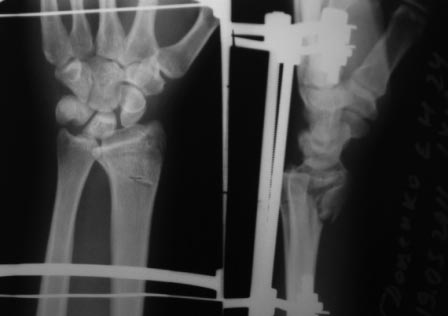

Нет не в вывихе, т. К. Из-за спицы проведенной через обе кости предплечья, то ротационные движения и подвижность локтевой кости резко ограничены, это может в некоторых проекциях расцениваться как подвывих, если найду покажу финальный снимок, там все рентгенологические показатели восстановлены.

Согласен с последним предложением относительно применения аппарата внешней фиксации. Повреждения луча по типу "переднего Бартона" очень хорошо закрыто устраняеются в АВФ, при этом завершающим элементом (после достижения репозиции посредством постепенной дистракции) может быть введение спицы с упором (конечно, вне проекции срединного нерва и сухожилий сгибателей пальцев)и обеспечение боковой компрессии переднего отломка к основному фрагменту.

АВФ очень разнообразны, мы (отделеие хирургии кисти ГКБ 4 г. Москвы) используем только две полудуги и две штанги смонтированные на двух спицах Киршнера, проведенных через кости предплечья и основания 2-5 пясьных костей (аппарат Лазарева-Коршунова), дополнительных спиц не проводим.